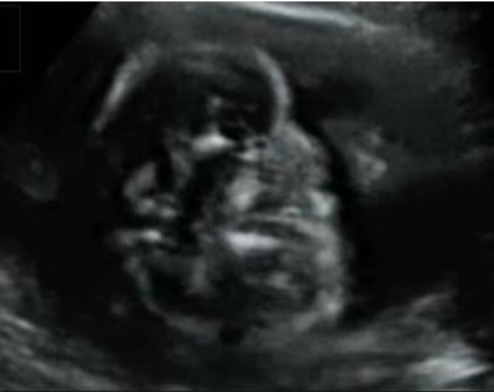

Guida al Counselling di Novembre 2025: estrofia della cloaca

vi presentiamo la guida al counseling di Novembre 2025 sull’estrofia della cloaca